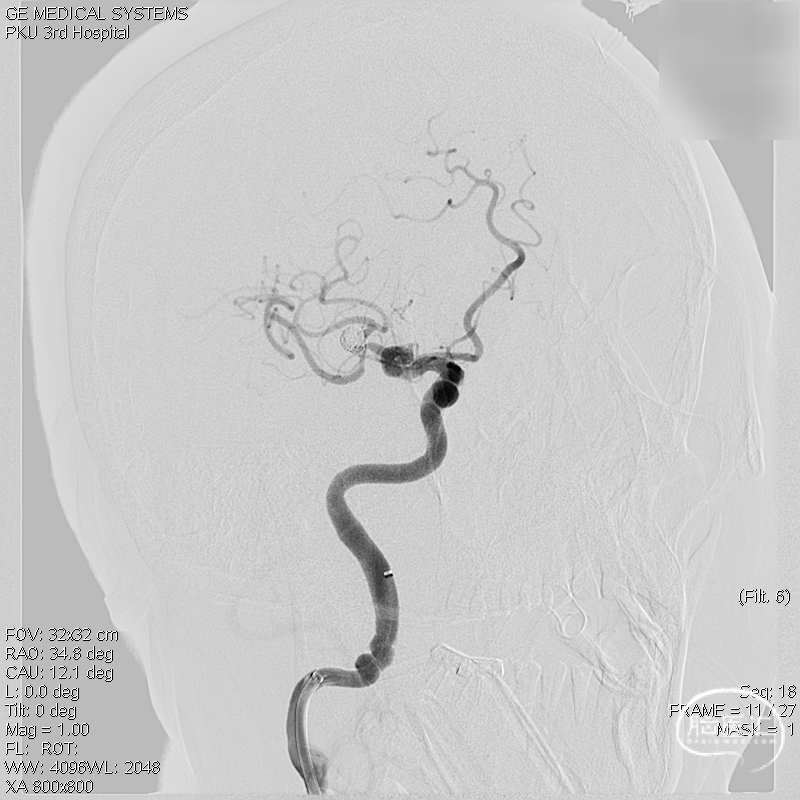

术前影像学检查:术前正侧位。

术前工作位与三维重建:显示右侧MCA分叉部未破裂动脉瘤,6.9mm*7.2mm,瘤颈7.4mm。该病例之困难在于M1迂曲成袢。